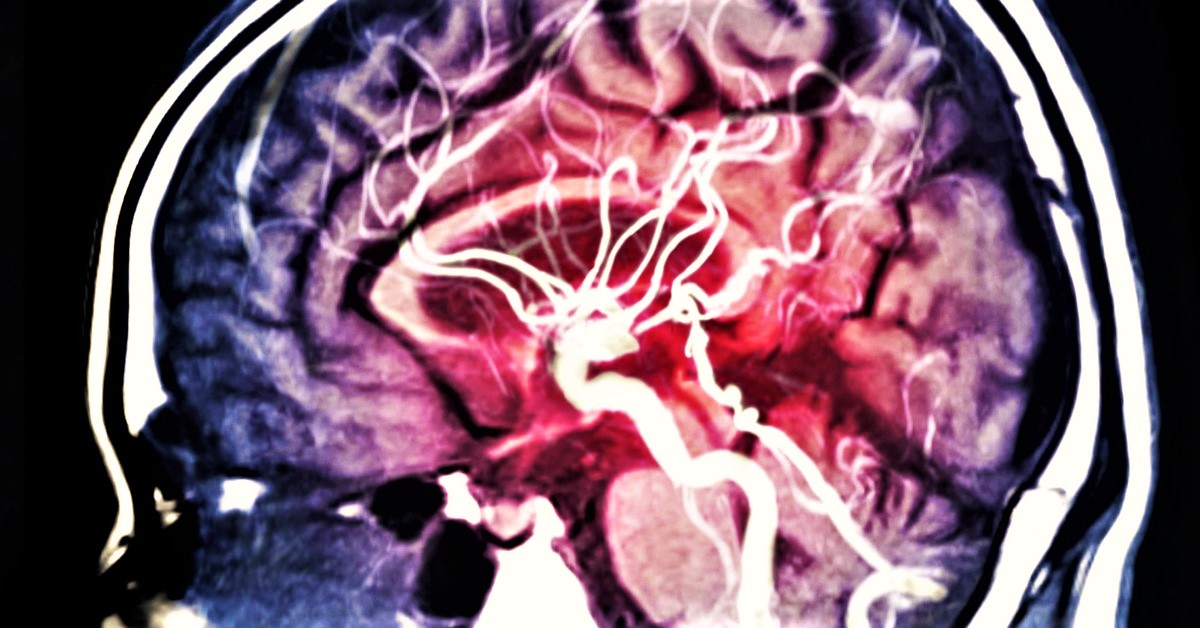

Egy különös ember, állat, vagy valami nyomasztóan közeledik feléd, üldözni kezd, rémülten menekülsz előle, mielőtt elkapna: felriadsz. Az álomfejtés nem újdonság, viszont egy új kutatás arra volt kíváncsi, hogy a rémálmok milyen hatással vannak az egészségünkre.